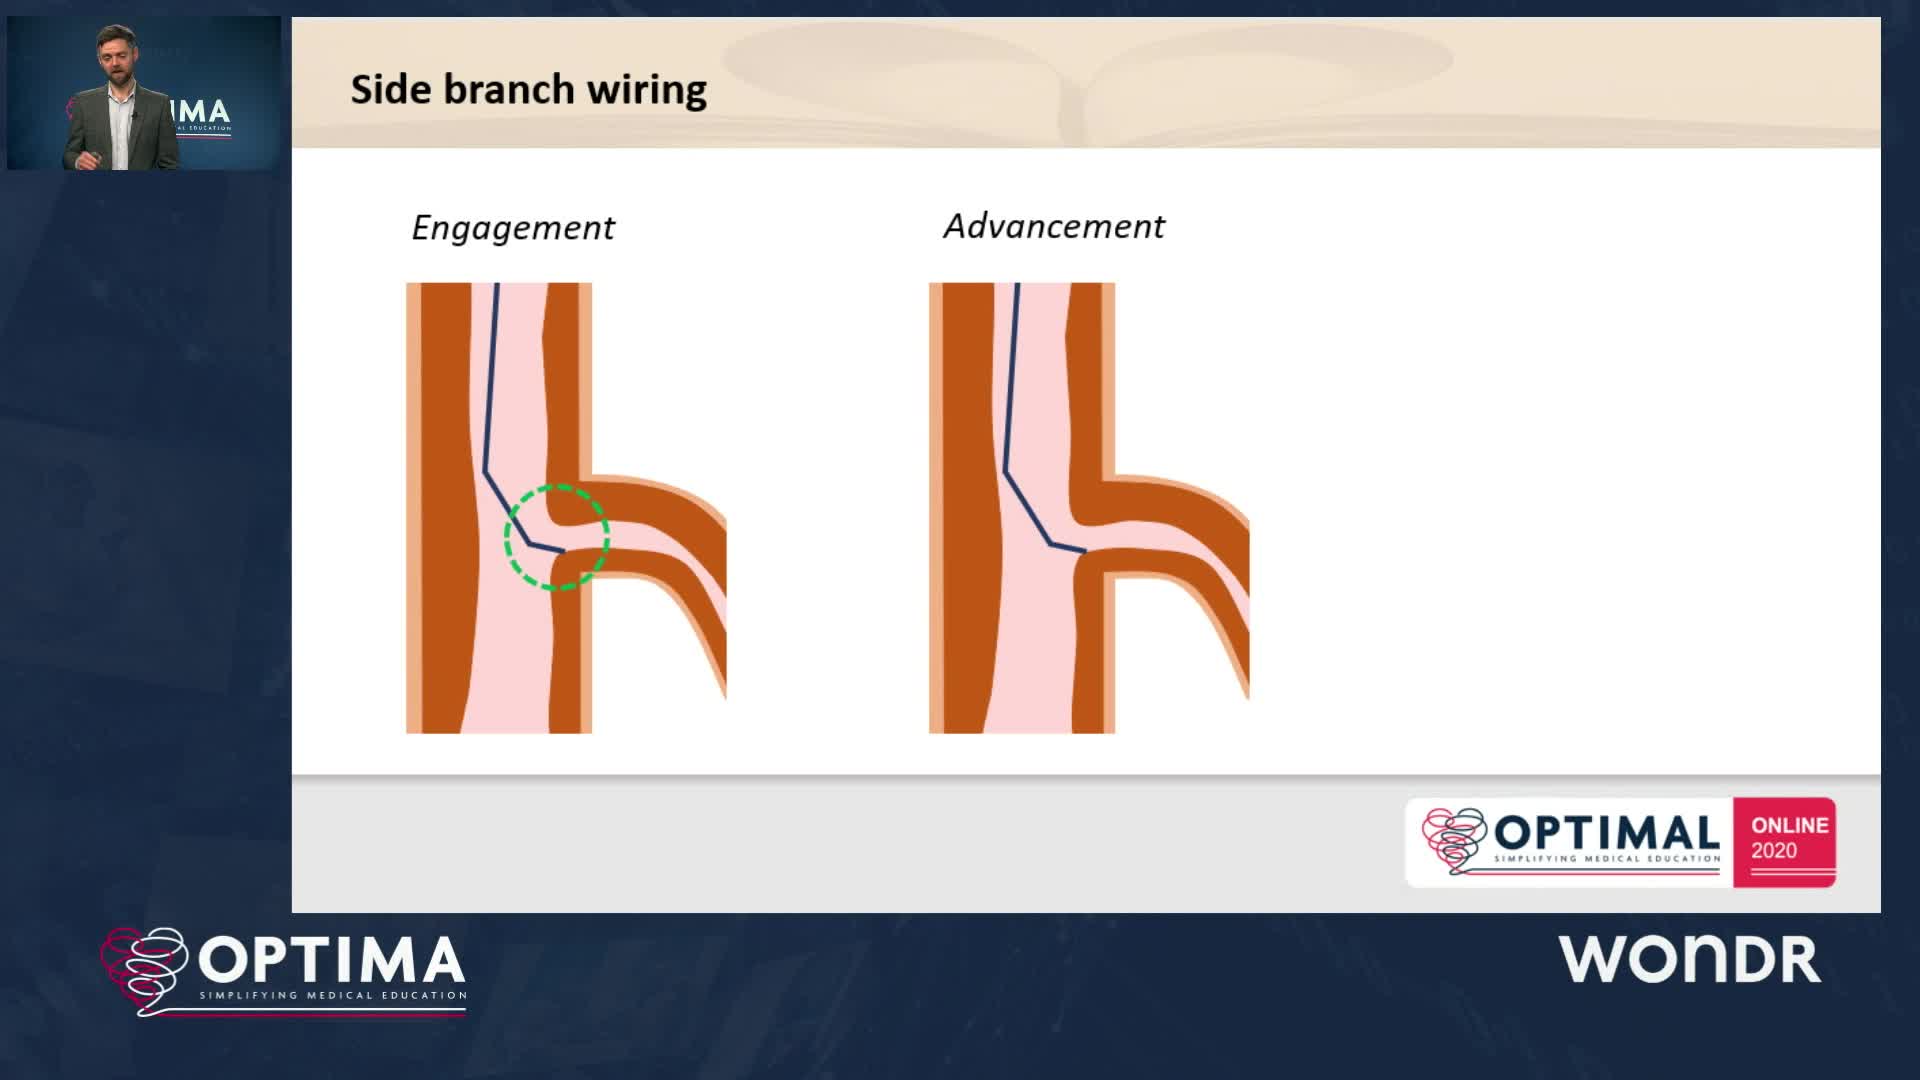

The integrated use of physiology and imaging is transforming the treatment of complex bifurcation disease. We explore...